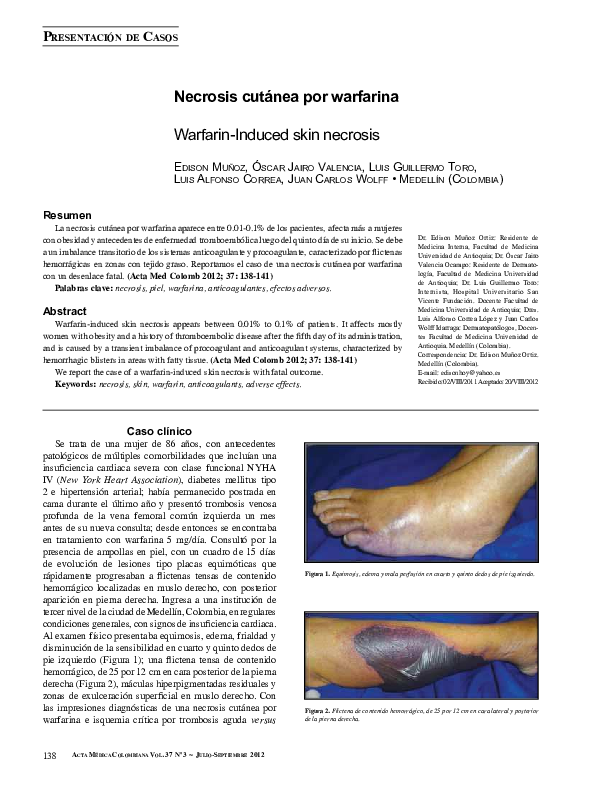

- Ampollas o úlceras: Pueden aparecer ampollas llenas de líquido o úlceras abiertas.